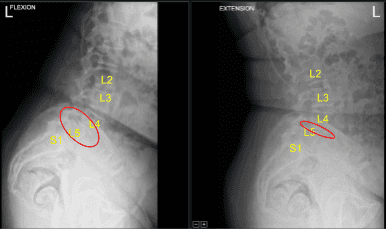

Anterolisthesis of L4 on L5 with dynamic instability during flexion and extension